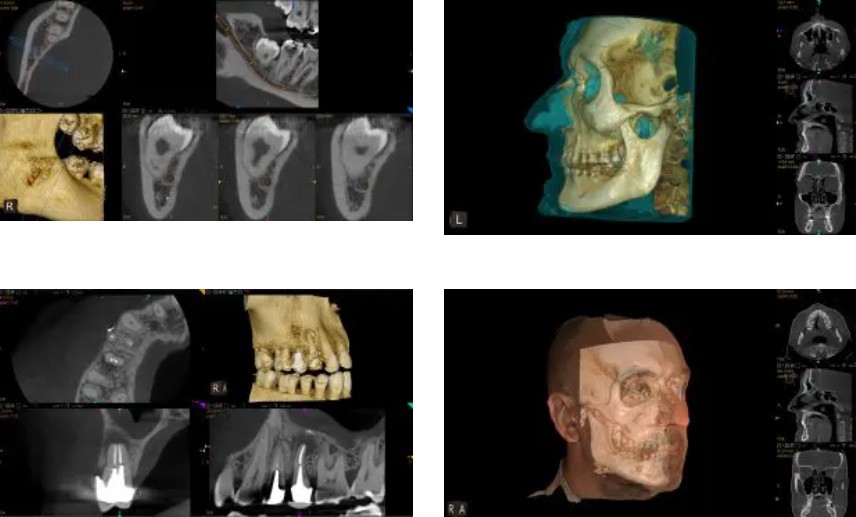

LARGE FOV CONE BEAM

The CS 9600 Premium delivers a broad range of cone beam configurations and field of view sizes (i.e. 4x4, 5x5, 6x6, 10x5, 8x5, 8x8, 10x10, 12x5, 12x10, 16x12, 17x16 cm) to support a variety of applications, from endodontics and single implants to airway studies, and everything in between. For added patient safety, select the low-dose mode to capture high-quality scans at doses similar to standard 2D panoramic images.

HIGH RESOLUTION SCAN

With image resolution up to 90 μm, the CS 9600 Premium cone beam system delivers superior quality high-resolution 3D scans, providing the anatomical details required for exams and treatment requiring exact precision and accuracy.

CS 3D IMAGING SOFTWARE

CS 3D Imaging Software, included with every CS 9600 3D purchase, has all the tools you need to efficiently capture, analyze, store, retrieve, and share both 2D panoramic and dental cone dental images with ease.